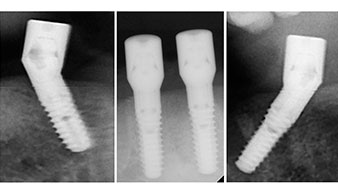

Para la planificación y la minimización del riesgo, se realizó una tomografía volumétrica tridimensional (TVD, Planmeca) que mostró que la calidad y la cantidad del tejido óseo era suficiente para la intervención quirúrgica y el tratamiento inmediato con el método Fast & Fixed. Siguiendo el protocolo de este método, se insertaron los implantes en la región de las piezas 35, 32, 42 y 45. Debido a la inclinación de hasta 45 grados de los implantes distales, el perfil de emergencia se desplazó hacia posterior y se generó un mayor polígono de soporte (fig. 3).

Este valor se corresponde con la posición siguiente del ajuste predefinido en Implantmed. Aquí se aprecia la inclinación de aproximadamente 45 grados del contra-ángulo de W&H hacia medio caudal en la región de la pieza 45 para preservar el nervus mentalis. El foramen mentale sirve como orientación anatómica para todas las perforaciones en esta zona. Las perforaciones siguientes se realizaron con una velocidad reducida de 300/rpm (figs. 10 y 11).

Para compensar la divergencia de los implantes distales, se atornillaron pilares acodados (35 grados) de forma que los perfiles de emergencia de todos los implantes quedaran en la posición más vertical posible en relación con la mordida. Este paso es necesario para poder atornillar de forma oclusal el tratamiento provisional y, posteriormente, el definitivo (figs. 15 y 16).